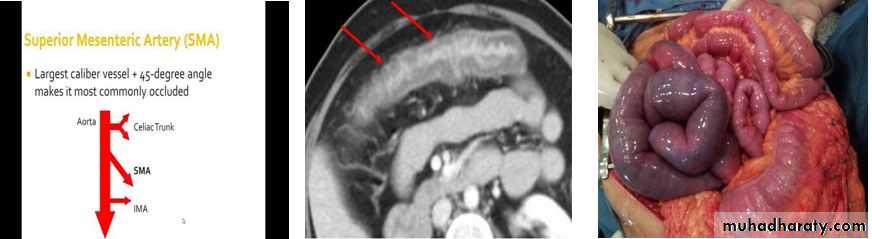

-An embolus from the heart or aorta to the superior mesenteric artery is responsible for 40–50% of cases, thrombosis of underlying atheromatous disease for approximately 25%, and non-occlusive ischaemia due to hypotension complicating myocardial infarction, heart failure, arrhythmias or sudden blood loss for approximately 25%. Vasculitis and venous occlusion are rare causes.

-The clinical spectrum ranges from transient alteration of bowel function to transmural haemorrhagic necrosis and gangrene. Almost all develop abdominal pain that is more impressive than the physical findings.

- In the early stages, the only physical signs may be a silent, distended abdomen or diminished bowel sounds, peritonitis only developing later.

-Leucocytosis, metabolic acidosis, hyperphosphataemia and hyperamylasaemia are typical.

-Plain abdominal X-rays show ‘thumb-printing’ due to mucosal oedema.

-Mesenteric or CT angiography reveals an occluded or narrowed major artery with spasm of arterial arcades, although most patients undergo laparotomy on the basis of a clinical diagnosis without angiography.

-Resuscitation, management of cardiac disease and intravenous antibiotic therapy, followed by laparotomy, are key steps.

- If treatment is instituted early, embolectomy and vascular reconstruction may salvage some small bowel.

-In these rare cases, a ‘second look’ laparotomy should be undertaken 24 hours later and further necrotic bowel resected.